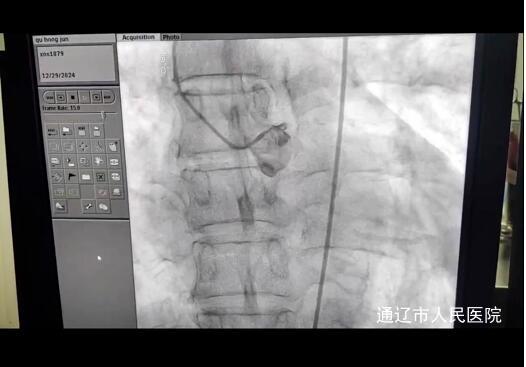

时间就是生命,我院立即对患者开通绿色通道,紧急行冠脉造影术,初期家属拒绝支架,返回CCU继续治疗,在李军主任及主治医生包瑞娜反复沟通下家属同意开通血管。心血管内三科郑崔成主任团队迅速行动,为患者行冠脉造影术及支架术,并行球囊扩张术,CCU配合心内三团队快速完成中心静脉置管,辅助放置IABP,术后进入CCU进一步治疗。